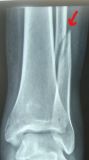

5. Delayed diagnosis of a lateral malleolus fracture in a 21-year-old male

Treatment: Open reduction internal fixation 20 days after the injury

I. Before surgery, lateral x-ray of the left ankle shows the site of fracture (red arrow) II. Four months post-surgery, lateral x-ray of the ankle shows the implant work with the union of the fracture (red arrow)